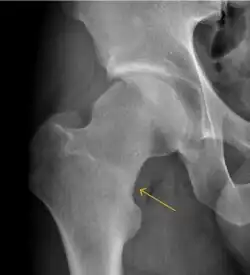

Slipped capital femoral epiphyses (SCFE)

Slipped capital femoral epiphyses (SCFE) usually affect 11- to 14-year-old adolescents (Figure 4). Radiographs may show widening and irregularity of the physis and posterior inferior displacement of the capital femoral epiphysis. On the AP view Klein’s line, tangent to the lateral aspect of the femoral neck, does not intersect the femoral head indicating that it is displaced. SCFE may compromise the blood supply to the femoral head and cause avascular necrosis, mainly when there is instability between the fragments.[1]